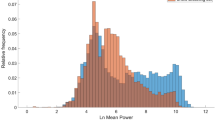

OSA children had longer obstructed breathing duration (OSA = 140.9 [86.6, 225.6], non-OSA = 23.3 [1.6, 61.2] min; p < 0.0001) and more obstructed breathing runs (OSA = 30.7 [19.9, 39.6], non-OSA = 6.1 [1.4, 13.7] runs/h; p < 0.0001); individually, snore and stertor were also significantly greater in OSA children. However, long periods (≥ 10 min) of obstructed breathing occurred in 69 (61.1%) and frequent runs (≥ 5/h) of obstructed breathing occurred in 63 (55.8%) of the 113 non-OSA children (Fig. 3).

Bubble plot showing total duration (log10, x-axis) plotted against number of runs (log10, y-axis) of obstructed breathing for each child. MOAHI values are on the z-axis; blue circles are non-OSA children with hotter colors and larger circles indicating increasing severity of OSA (all MOAHI values ≥ 10 events/h have the same diameter). Red dashed lines indicate thresholds of 10 min (x-axis) and 5 events/h (y-axis). MOAHI mixed and obstructive apnea/hypopnea index

Our results in this large group extends previous work in which the method was validated against PSG [7] and confirms that obstructed breathing predominates as an indicator of pediatric SDB. Quantification of obstructed breathing identified 98% of OSA children with only 2 children crossing one, but not both obstructed breathing thresholds (Fig. 3). Thus, the absence of obstructed breathing could be used to discount the presence of OSA. Most importantly, OSA and non-OSA children were frequently indistinguishable regarding the frequency and duration of obstructed breathing and many symptomatic children did not have OSA or obstructed breathing.